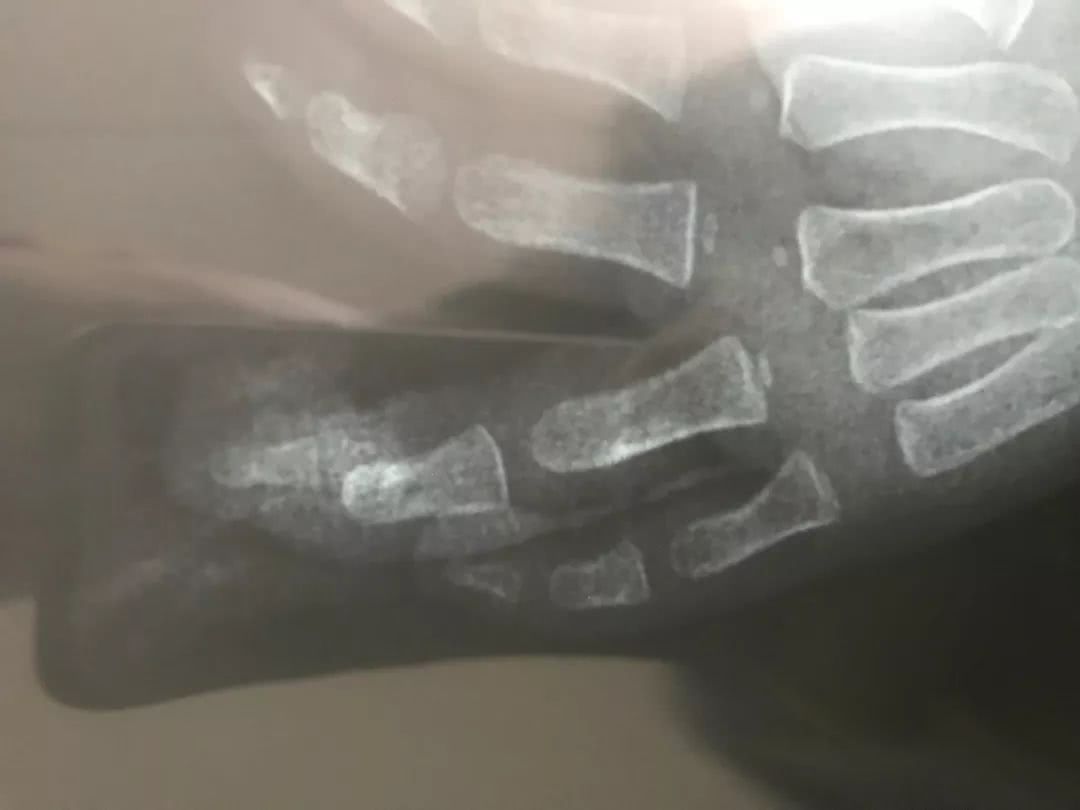

(聰聰手指已出現明顯骨折)

采訪中,市一醫骨科彭亮副主任告訴記者,事發當時聰聰的傷情較為嚴重,經初步診斷,發現聰聰左手無名指的遠端指骨骨折,神經血管受損,同時還伴有關節脫位的情況,如不及時手術,很可能留下殘疾。所幸,在經過近2個小時的手術后,聰聰的斷指最終算是保住了。